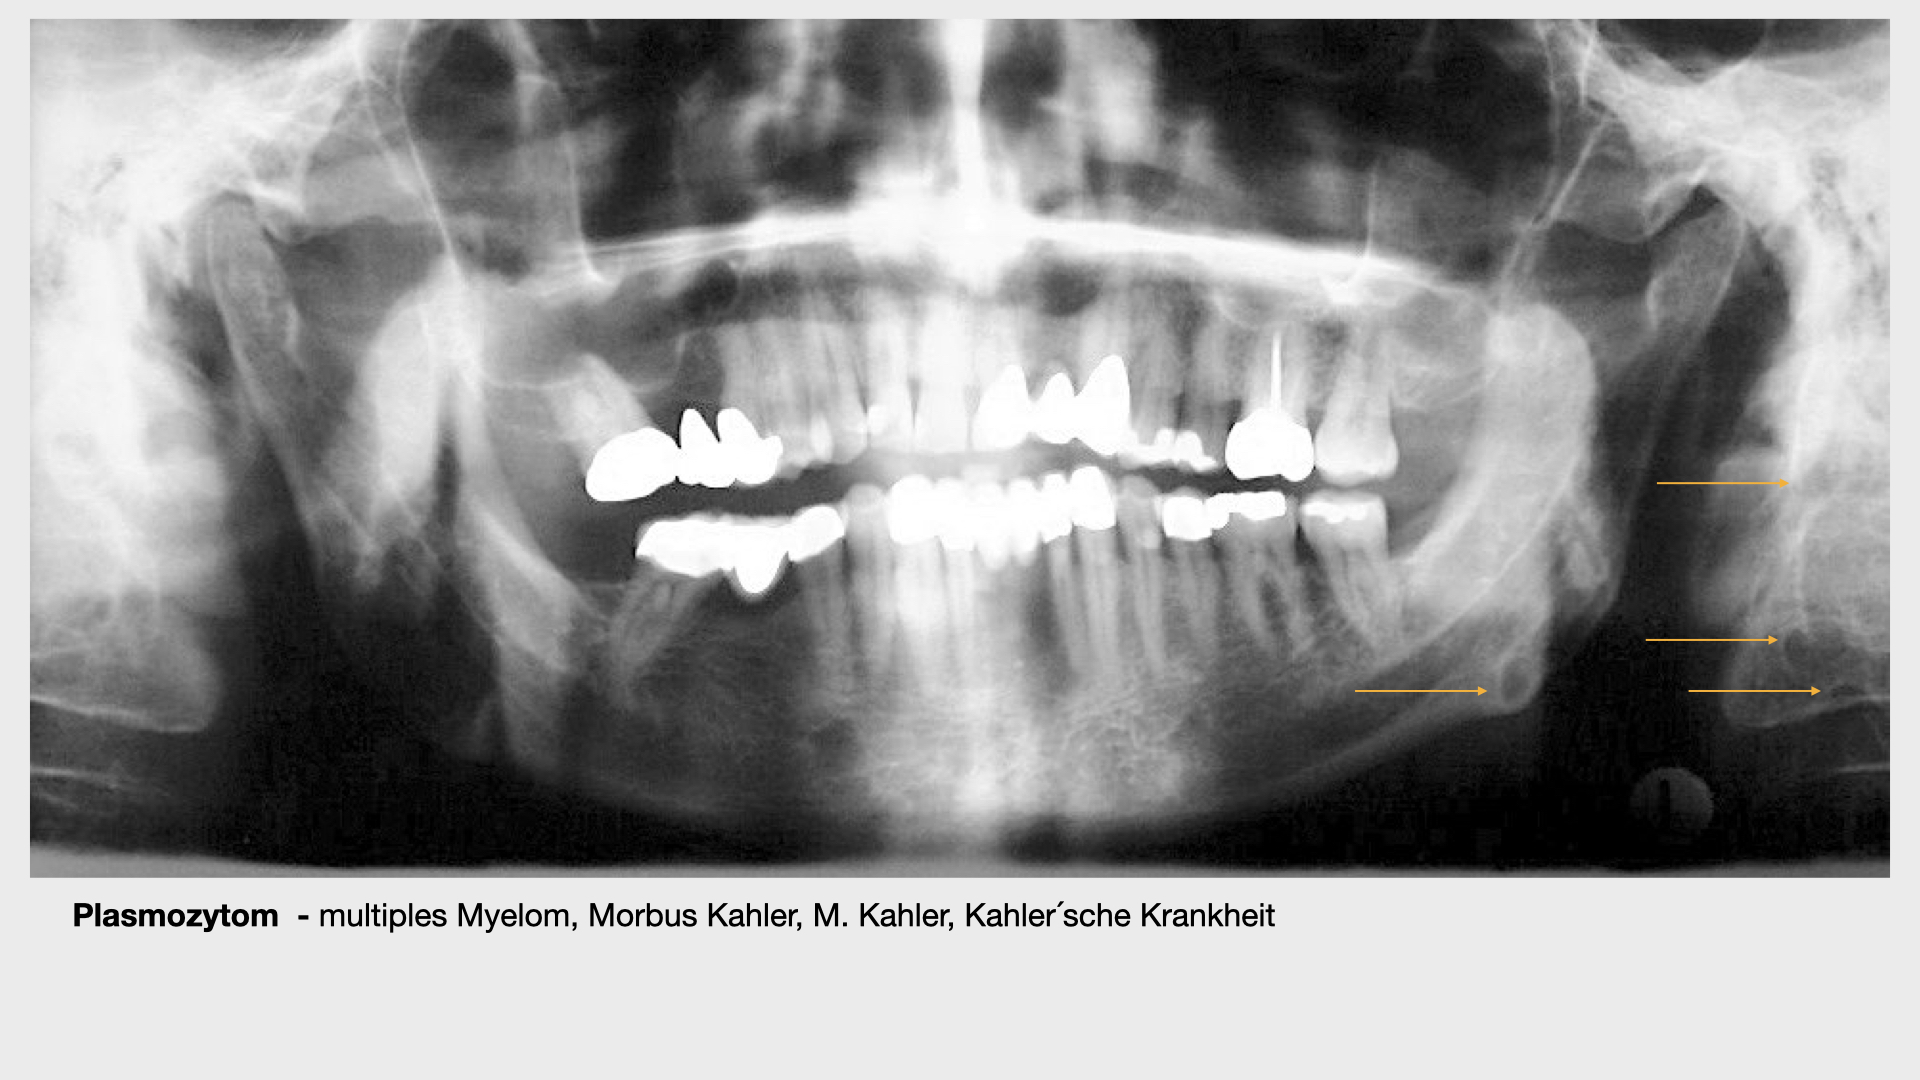

Plasmozytom.002

Plasmozytom / multiples Myelom